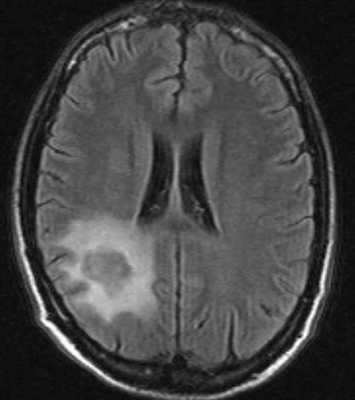

МРТ головного мозга. Аксиальная Т2-взвешенная МРТ. Расширение борозд и диффузные очаги.

МРТ головного мозга. Т2-взвешенная аксиальная МРТ. Токсоплазмоз.

МРТ головного мозга. Т2-взвешенная аксиальная МРТ. Лимфома.